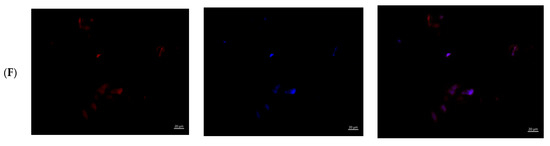

Results of Fluorescence Microscopy—Qualitative Analysis